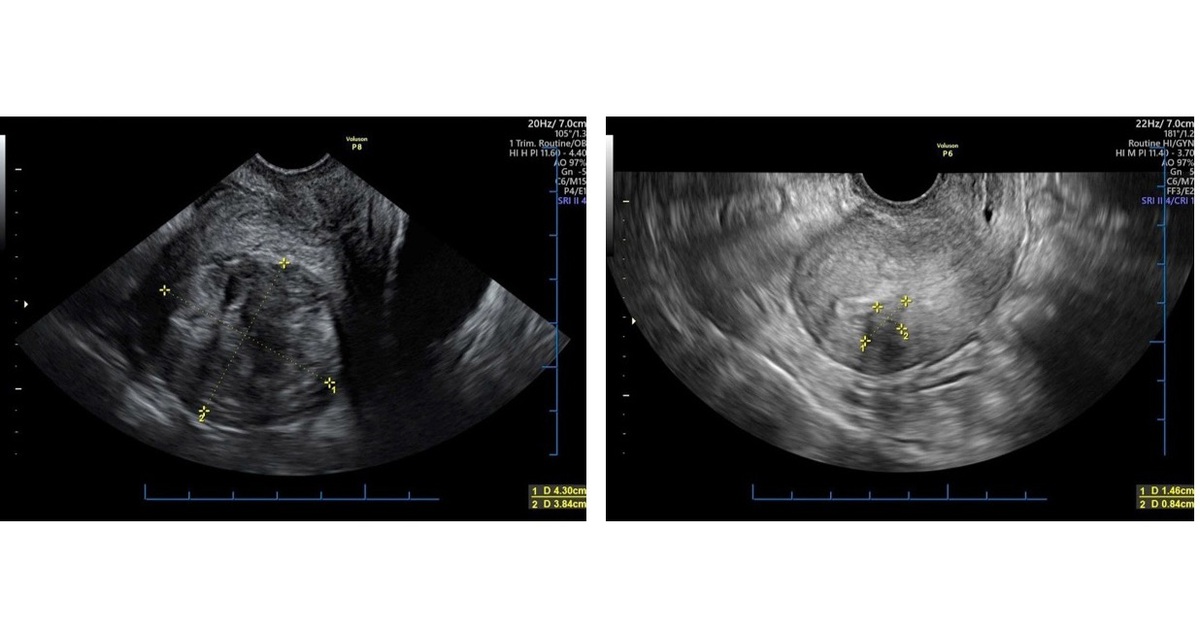

Chất lượng trứng và tình trạng tử cung: Để đạt tỷ lệ thành công cao, cần có 1-2 nang noãn đạt kích thước tiêu chuẩn vào ngày kích thích rụng trứng, và nội mạc tử cung phải đủ tốt.